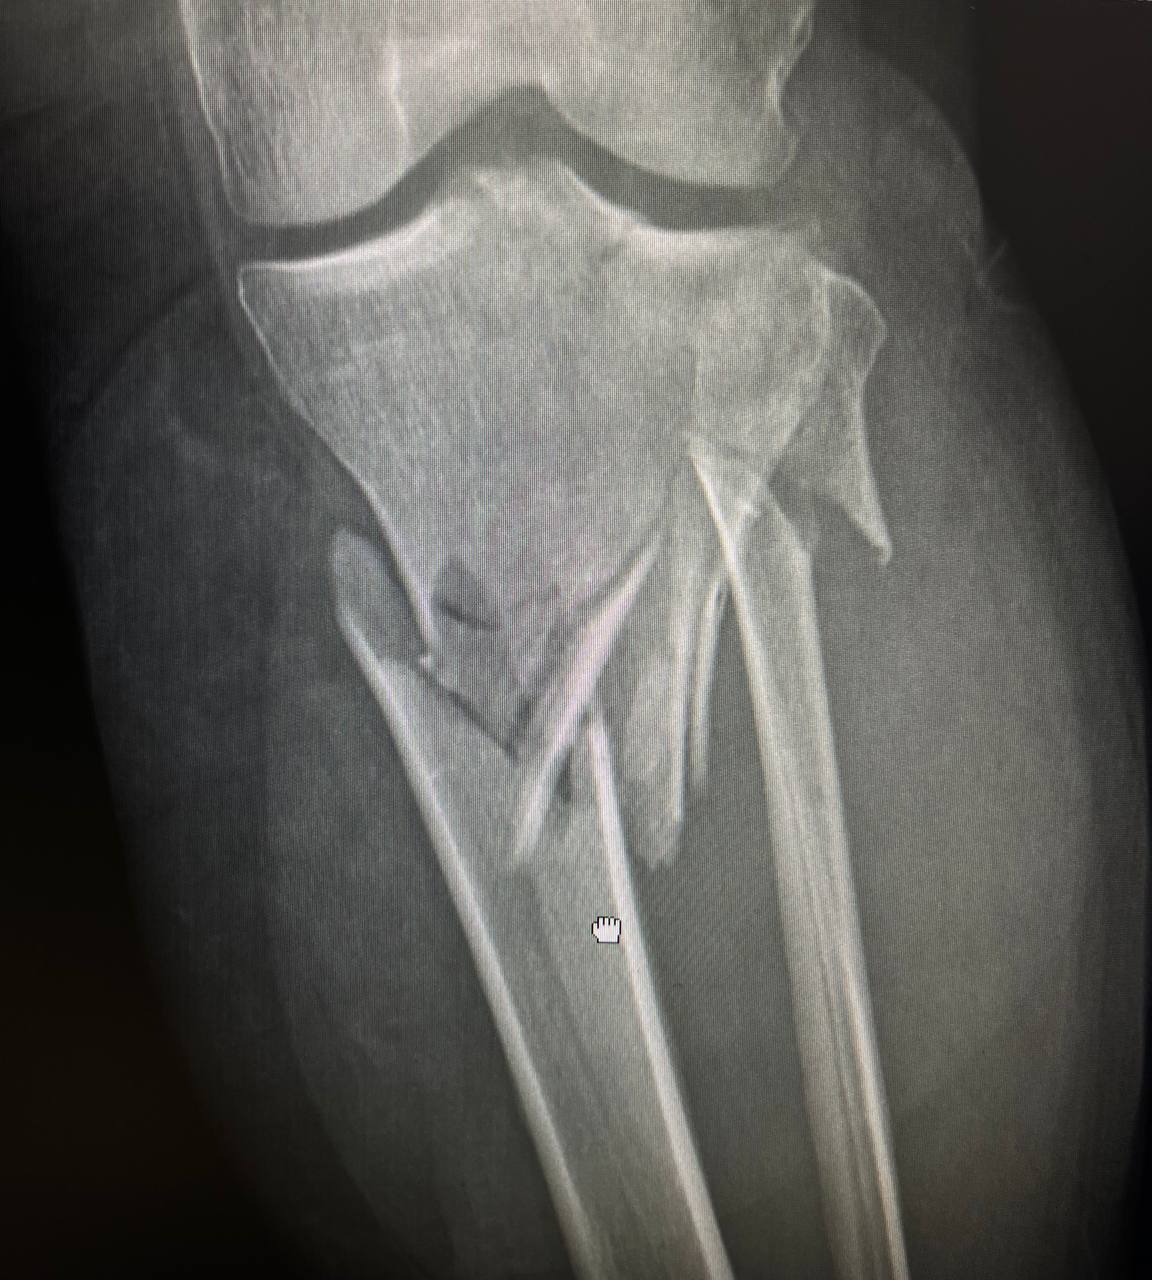

Під час обстежень було діагностовано багатоуламковий перелом в/3 лівої гомілки.

На момент поступлення у пацієнтки наявні симптоми розвитку компартмент-синдрому, це стан при якому набряк мʼяких тканин настільки сильний, що вони починають здавлювати самі себе, що може призвести до важких ускладнень в тому числі і ампутації . Тому при поступленні пацієнтці було проведено ургентну операцію – стабілізацію перелому апаратом зовнішньої фіксації та фасціотомію.